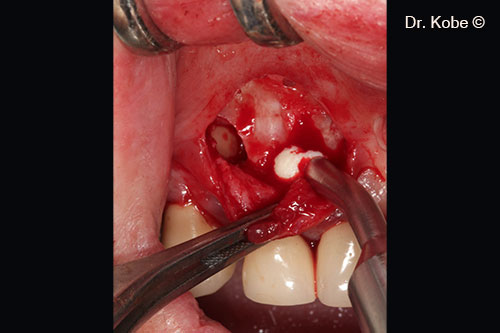

Horizontal incision (NIPSA) in the vestibule

Access to the defect